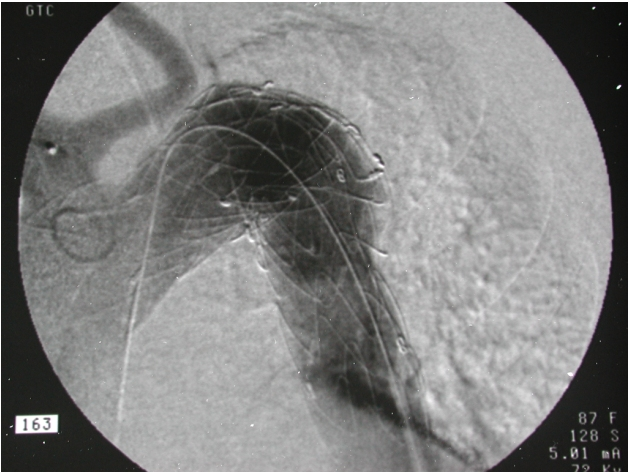

Usually the right femoral artery was exposed by cutdown and controlled proximally and distally. Nearly in all cases a 0.035 inch Terumo guidewire (Terumo®, Frankfurt am Main, Germany) was inserted over a sheath and positioned in the ascending aorta. This was followed by the introduction of a 6-F pigtail catheter and an angiography (Figure 1 [Fig. 1]) of the aortic arch and the descending aorta using a high pressure injection-pump with a non-ionic contrast medium (Imeron®, Altana Pharma, Germany). After marking the aortic arch with its branches as well as the descending aorta and the landing zone on the screen, a stiff guide wire was inserted and the angiography catheter removed. A delivery sheath (22, 24 or 25 F) was introduced with the punction of the common femoral artery. After pharmacologically controlled hypotension was induced (RR <80 mmHg), the stent graft was deployed under X-ray guidance (Figure 2 [Fig. 2]). The proximal and distal end of the device were dilated using a catheter to achieve optimal graft contact to the aortic wall. A final arteriogram verified sealing of the aortic lesion. The introducer sheath was removed and the artery sutured. Wound closure completed the procedure.

Figure 2: Intraoperative x-ray of stent graft, guide wire inside stent lumen